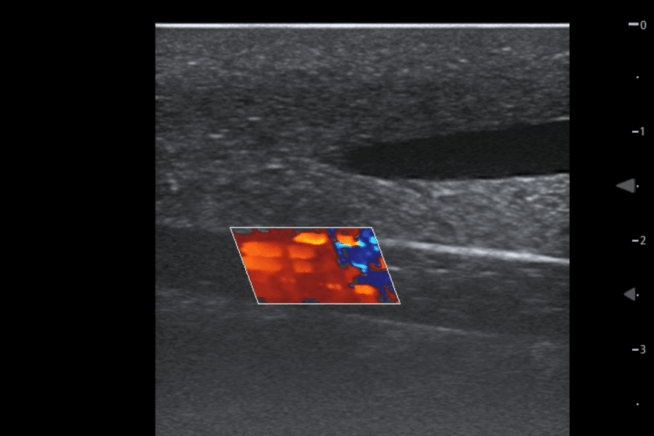

The TruUltra material is unlike anything else in the market. It showcases a high-quality ultrasound image to provide trainees with a true-to-life ultrasound training solution. Learners will benefit from realistic visualisation of the internal jugular and subclavian veins, carotid and subclavian arteries.

TruCVC® ideal for ultrasound-guided central venous catheterisation training, enabling consistent practice of needle insertion, guidewire handling, and full catheter placement using the Seldinger technique – supported by realistic anatomy, visual flashback, and rapid reset for repeatable learning outcomes.

Yes, real feel vascular tenting will be experienced upon entry into a vessel and fluid can be withdrawn if the procedure is successful. You can also simulate a pulse through simple hand pump provided with the product.